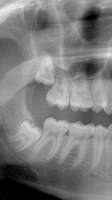

Сап медач. Релейтед — снимок моих зубов. Очень Аноним 31/01/17 Втр 23:04:55  567459

tmp19690-Screen[...].png (621Кб, 1080x1920)

Сап медач.

Релейтед — снимок моих зубов.

Очень хочется узнать, это зубы мудрости причиняют такой лютый дискомфорт?

Из-за них остальным не хватает места и всё перекосилось?

Верхний уже в гайморовой пазухе?

Какие будут подводные камни, если их удалят?

Ох ебать, снимок почти как мой. Тупо пиздуй и удаляй как можно быстрее, да, зубы искривлены из-за растущих восьмёрок, а потом будет ещё хуже, вплоть до того, что может встать необходимость установки брекетов. Я сам тянул, пока не почувствовал, что восьмерка реально давит. Удалил недели 2 назад, всем доволен, десна ныла первые 5 часов, потом лёг спать и на следующий день нихуя не было нужно, даже анальгетик купил впустую получается, лол

Судя по снимку там тебе нехилое дупло сделают, прежде чем вырвать его (нижний), ыыыы

Не боись, дружище - были у меня целых две таких нижних восьмерки - одну удалил лет 12 назад, вторую - только в этом году. Если честно - пздц процедура, но главное - реабилитационный период. У меня восьмерка лежала на нерве, после удаления пропал вкус с левой стороны. Ну то есть анестезия отпустила, чувствительность вернулась, холодное-горячее - все в норме, а вкусовые рецепторы оказались отключены. Я чуть кирпичей не выложил от впечатлений. Длилось месяца три, потом начало покалывать слева, перешло в как бы прострелы в десне - вкус полностью восстановился в итоге. Зато теперь с зубом мудрости проблема навсегда решена. По поводу верхней - обычно намного проще их удалять, но у тебя она неритинированная, придется десну разрезать, похоже.